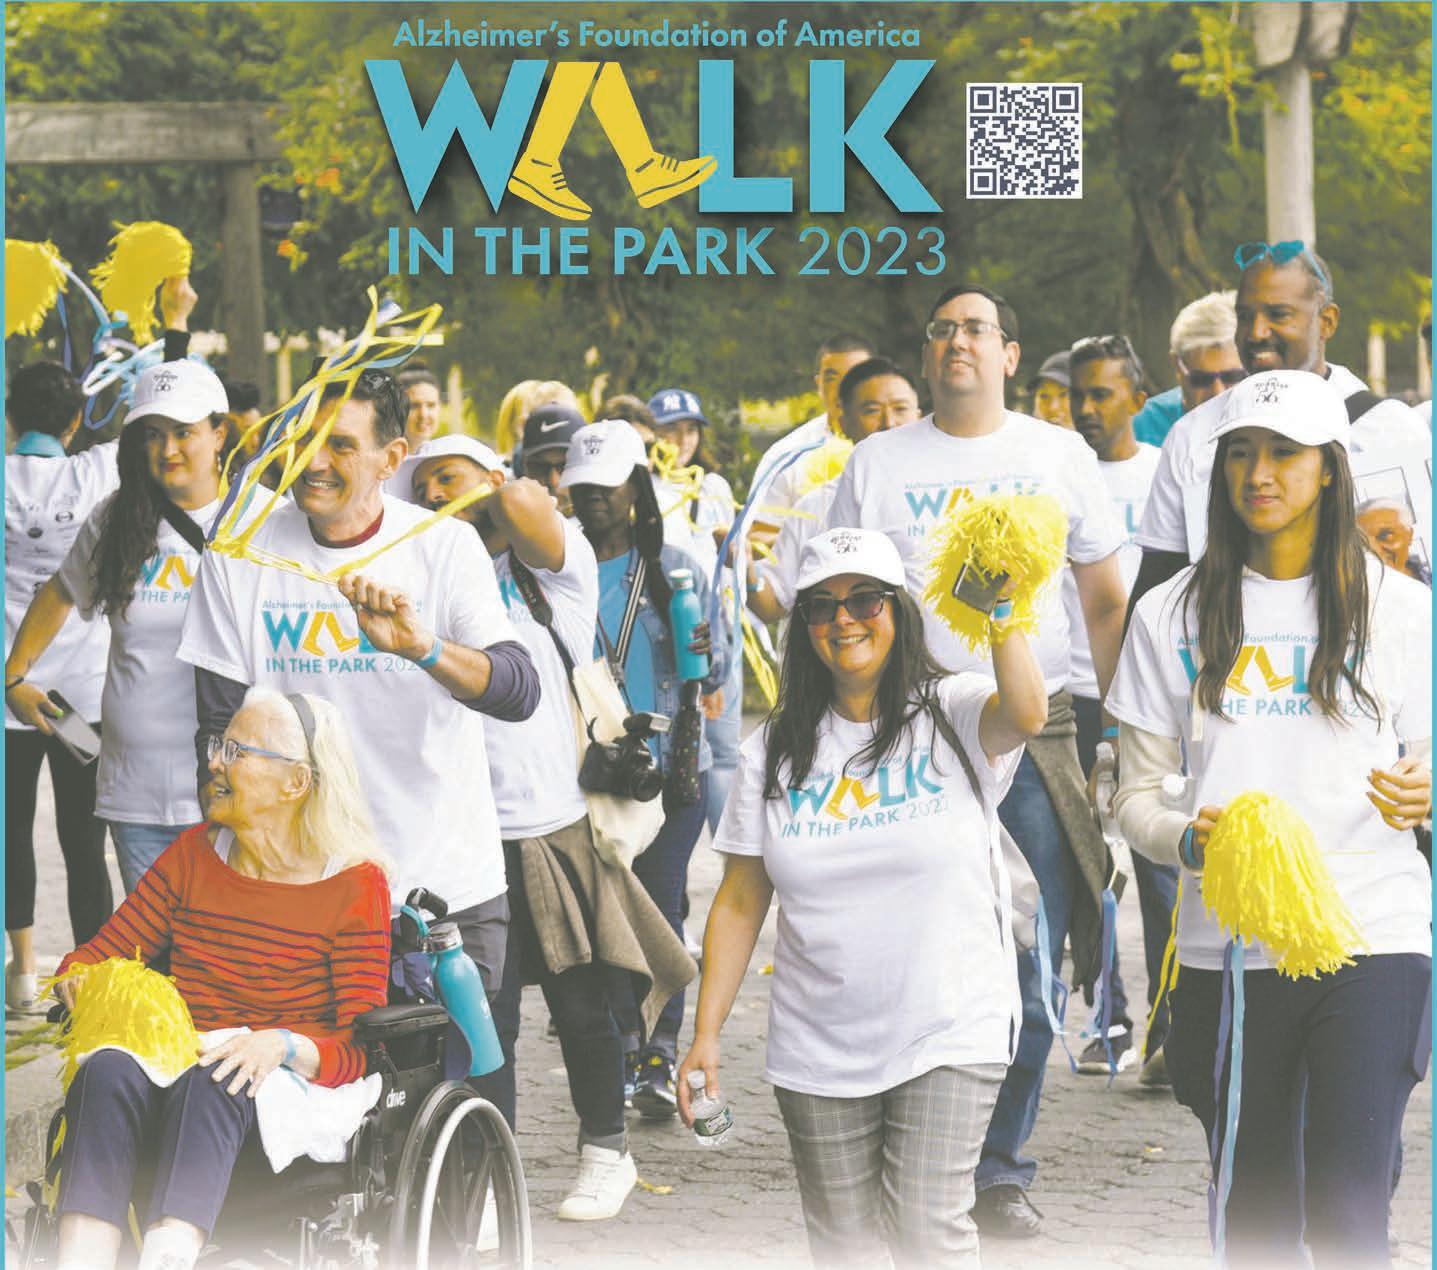

In this series, we’ve explored how cannabis left its mark in , how the Shinnecock

Nation plans to help bring medicinal and adult-use (or ‘recreational’) cannabis to Long Island residents, and how finding success with today’s legal market may have everthing to do with real estate, regulations, and learning from history.

The first three parts of this four-part series also frequently made reference to the fact that cannabis is, in addition to being a source of protein and fiber and cultural mainstay, a powerful and generally safe source of medicine, with dozens of known medicinal applications and likely plenty more we don’t know about yet. This fact is evinced not just by bountiful contemporary testimony from patients and doctors across the country, or by the millions (if not billions) of dollars that big companies have poured into medicinal cannabis operations, but also by the fact that major American pharmaceutical players, as well as the United States federal government itself, have laid claim to the plant and its uses.

To wit: for nearly 20 years, the National Institute of Health has held a patent on certain cannabinoids as related to their anti-inflammatory properties and capacity for treating oxidative stress in the body, as related to stroke, autoimmune disorders, aging, and so on. And in fact, our nation has known that cannabis is a medicine (and a relatively quite safe one, at that) for well over a hundred years, and yet has prohibited its use and sale since the 1930s, with dramatic impacts for patients, doctors, and medicine as a whole, and for the Black and brown communities who have consistently been criminalized over cannabis.

A 1913 product label describes Eli Lilly’s “Cannabis Americana” medicinal extract. (Credit: Patients Out Of Time)